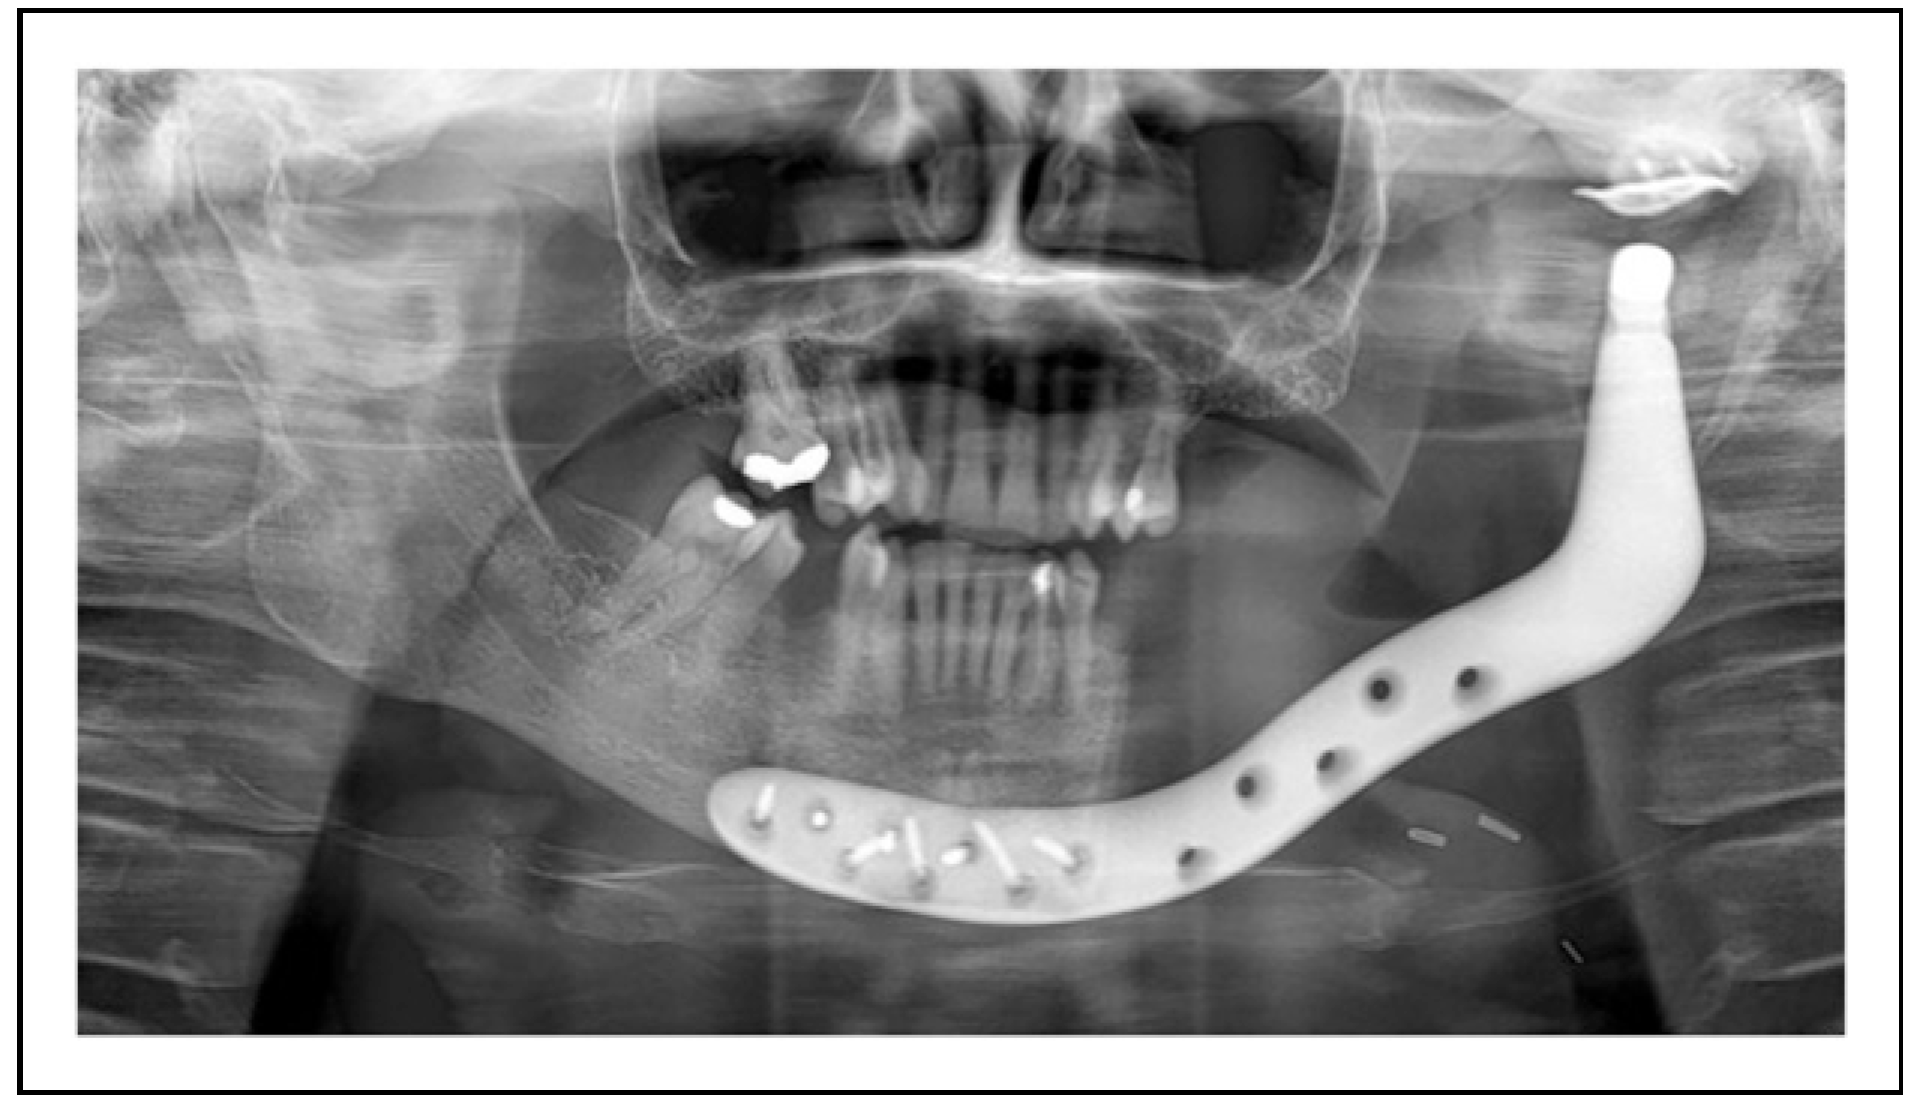

Bilateral TMJ Replacement With Complete Replacement of the Mandible, Patient 8